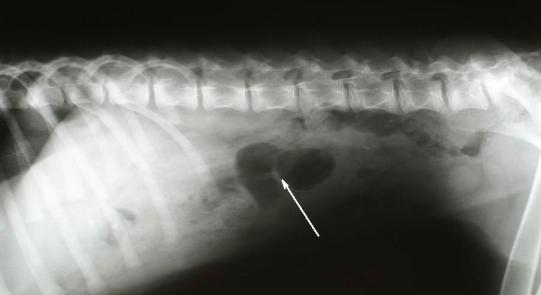

Bei akutem Erbrechen kommt als Ursache insbesondere bei Junghunden immer auch eine Aufnahme von Fremdmaterial (Fremdkörper, aber auch reizende Substanzen) in Frage. Aus diesem Grund wird die Bauchhöhle von „Szana“ genauer untersucht. Auf der Röntgenaufnahme sind keine Hinweise auf einen Fremdkörper sichtbar; allerdings sind bei dieser Methode primär nur röntgendichte Materialien (Stein, Metall, z.T. auch Kunststoffe) sichtbar. Deswegen wird bei Röntgenuntersuchungen auch auf indirekte Zeichen eines Fremdkörpers (Hinweise auf einen Darmverschluss, zum Beispiel streckenweise aufgegaster Dünndarm) geachtet. Das Röntgenbild zeigt zwar ein aufgegastes Stück Darm (Pfeil), welches aber höchstwahrscheinlich durch den Blinddarm gebildet wird und damit nicht von Bedeutung ist.